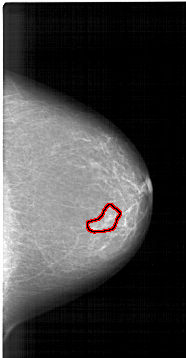

A_1422_1.RIGHT_CC

RIGHT_CC LINES 6076 PIXELS_PER_LINE 3151 BITS_PER_PIXEL 12 RESOLUTION 43.5 OVERLAY

FILE: A_1422_1.RIGHT_CC.OVERLAY

TOTAL_ABNORMALITIES 1

ABNORMALITY 1

LESION_TYPE MASS SHAPE IRREGULAR MARGINS ILL_DEFINED

ASSESSMENT 4

SUBTLETY 1

PATHOLOGY BENIGN

TOTAL_OUTLINES 1

BOUNDARY